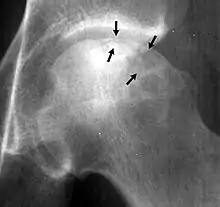

In radiology, the crescent sign is a finding on conventional radiographs that is associated with avascular necrosis.[1][2][3] It usually occurs later in the disease, in stage III of the four-stage Ficat classification system.[1] It appears as a curved subchondral radiolucent line that is often found on the proximal femoral or humeral head.[1] Usually, this sign indicates a high likelihood of collapse of the affected bone.[1] The crescent sign may be best seen in an abducted (frog-legged) position.[1][4]

The crescent sign is caused by the necrotic and repair processes that occur during avascular necrosis.[1][2] Osteosclerosis occurs at a margin where new bone is placed over dead trabeculae.[1] When the trabeculae experience stress leading to microfractures and collapse, the crescent sign appears.[1]